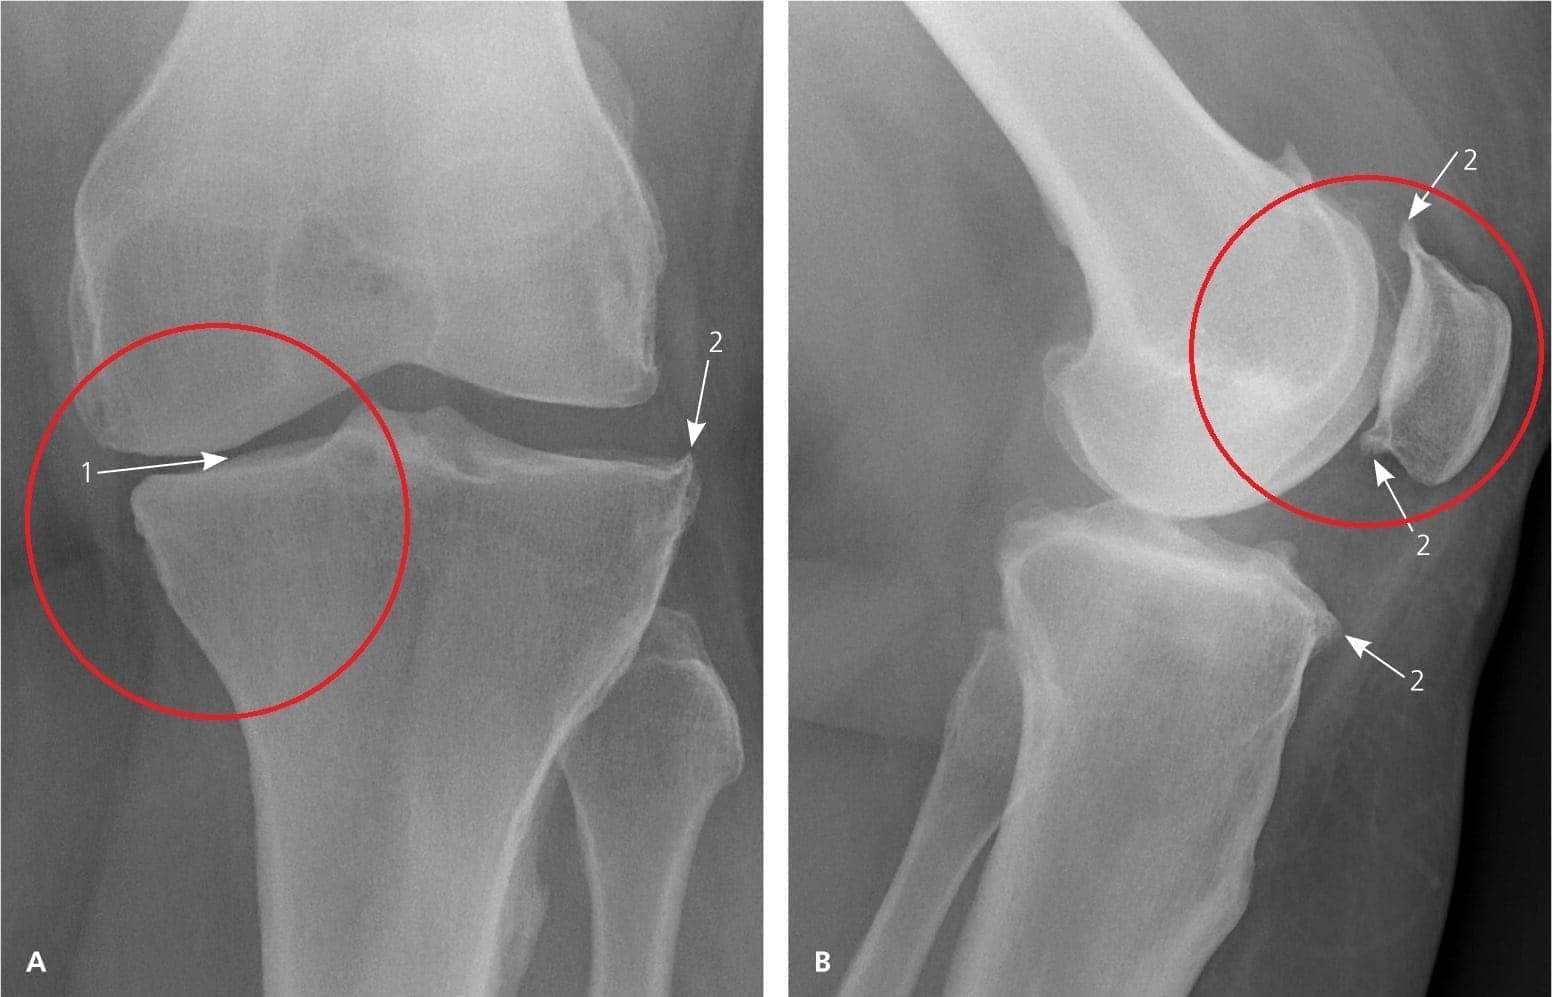

Встретила меня ну очень пожилая врач и, ничего не говоря, отправила меня на рентген и анализы крови/мочи. На втором приеме за пару минут поставила мне диагноз – вторичный артроз с какими-то осложнениями. Я, честно говоря, не очень понимала, что она говорит. Что-то она там мне сбивчиво объяснила, выписала кучу лекарств и отправила домой.

image

8-я неделя: сдала анализы и сделала рентген. Никаких следов артроза! Хрящи в суставах как у 20-ти летней девчонки. Докторша сказала, что на предыдущем рентгене скорее всего был дефект, поэтому диагноз артроз был ошибочным.